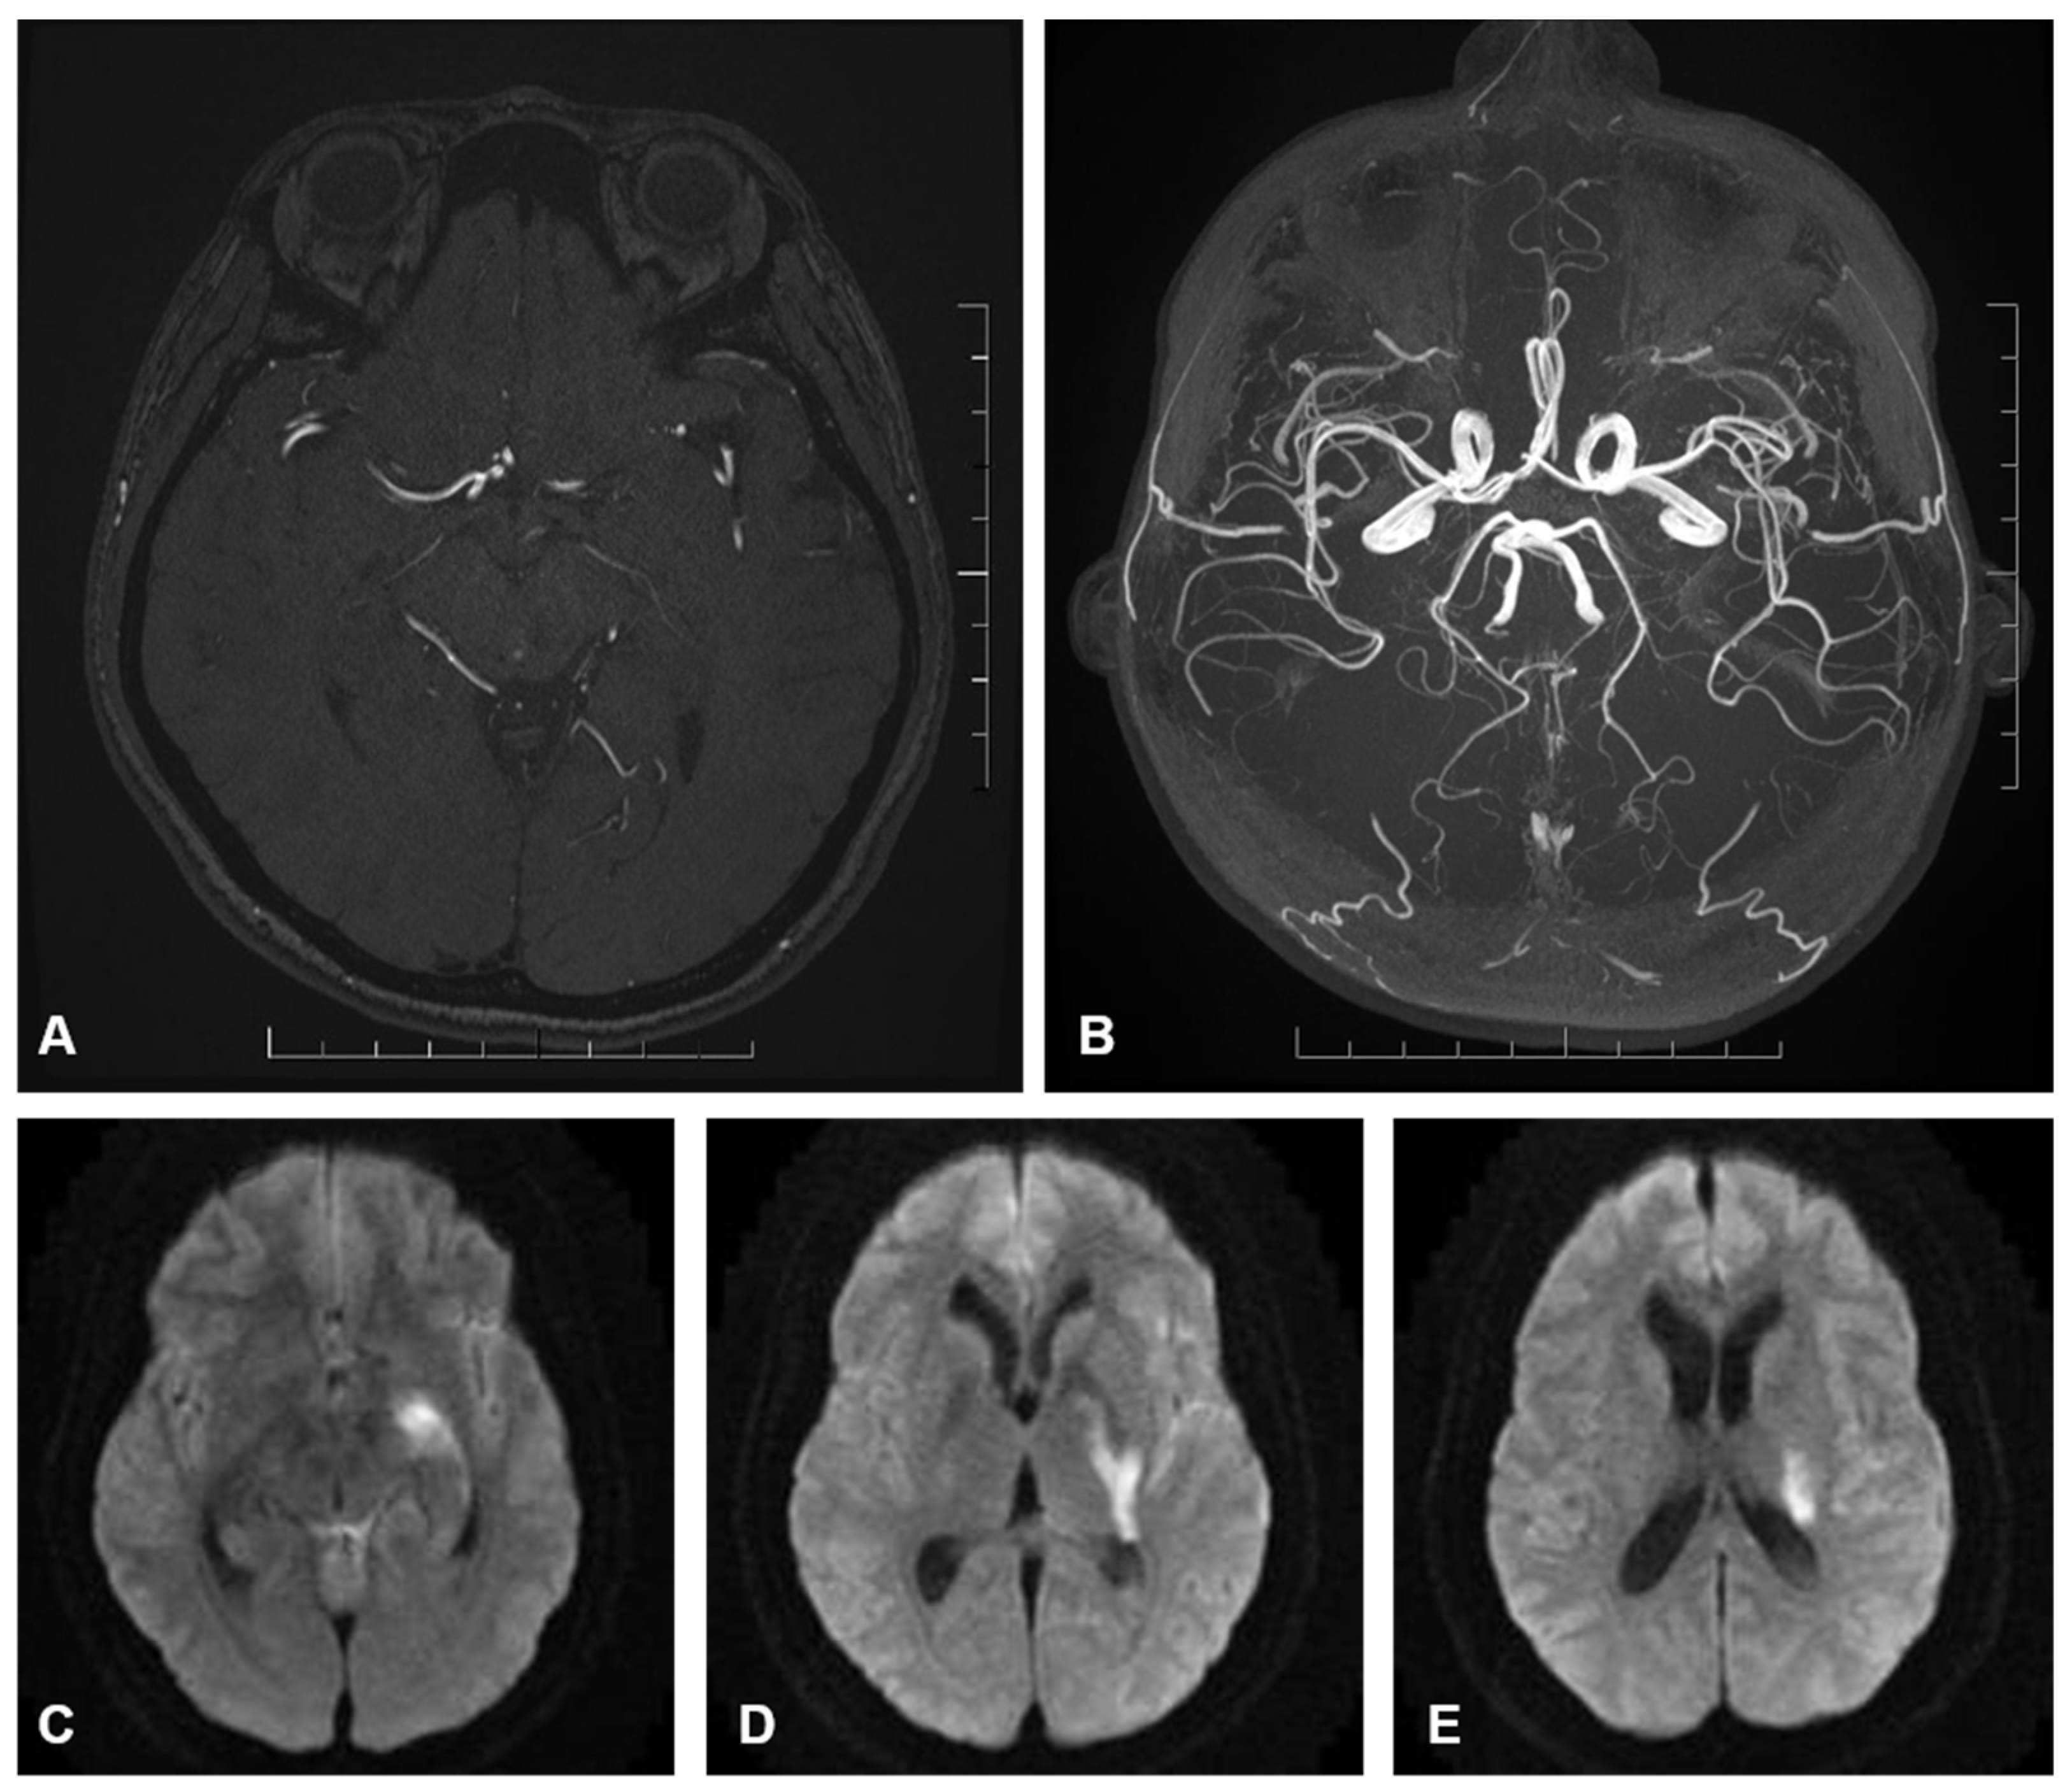

Within the clipping cohort, both patients had AChoA territory infarcts. The post-procedural mRS were 5 and 3, respectively (Figure 2).

4.1. Anterior Choroidal Artery Anatomy

AChoA arises from the dorsal surface of the ICA (Internal carotid artery) in 98% of cases [4,6]. The cisternal segment traverses the carotid and ambient cisterns, where perforating arteries originate [7]. These perforators supply eloquent structures, including the optic tract, internal capsule (posterior limb, genu, and retrolenticular parts), globus pallidus, caudate tail, lateral thalamus, cerebral peduncle, hippocampus, and amygdala [8,9]. The choroidal segment traverses the choroidal fissure, entering the temporal horn to supply the choroid plexus and anastomose with the choroidal system (Figure 1).

Figure 2. (A) axial image of a contrast enhanced MR intracranial angiogram which demonstrates the course of the AChoA. The artery gives rise to multiple perforators as it traverses the carotid, ambient and choroidal cisterns which may supply adjacent eloquent structures including the optic nerve, medial temporal lobe and middle cerebral peduncle. (B) axial image of a maximum intensity projection of the same contrast enhanced MR angiogram which demonstrates the path of the AChoA in relation to the anterior and posterior circulation. (CE) B1000 diffusion weighted axial images of the brain arranged caudal to cranial. These panels demonstrate restricted diffusion (hyperintensity) involving the AChoA territory in keeping with acute infarction.There is involvement of the hippocampus/mesiotemporal lobe (C), internal limb of the internal capsule encroaching on the lateral thalamus (D), and the corona radiate extending towards the caudate tail (E).